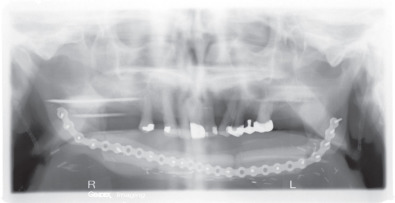

To maintain proper alignment of the mandibular segments during mandibular surgery, the utilization of fixation plates and screws is a commonly available technique. If no mandibular reconstruction is being planned due to the amount of tissue loss, the removal of the condyle and the remaining ramus on the affected side should be completed, to prevent the medial migration towards the maxilla, and decrease the chances of complications due to compromised function and prosthetic rehabilitation.

Reconstructive surgery using free flaps and bone transplantation has greatly improved the surgical outcome for patients requiring a surgical procedure, which will affect the continuity of the mandible ( Fig. 3.11.3 ). Virtual surgical planning utilizing CT scans can also allow the members of the surgical and reconstructive team to rehearse the procedures to be done, and evaluate the outcome. This has become an invaluable tool, allowing for the fabrication of individualized reconstruction plates, cutting guides for the harvesting of bone grafts, and stents for the placement of osseointegrated dental implants.